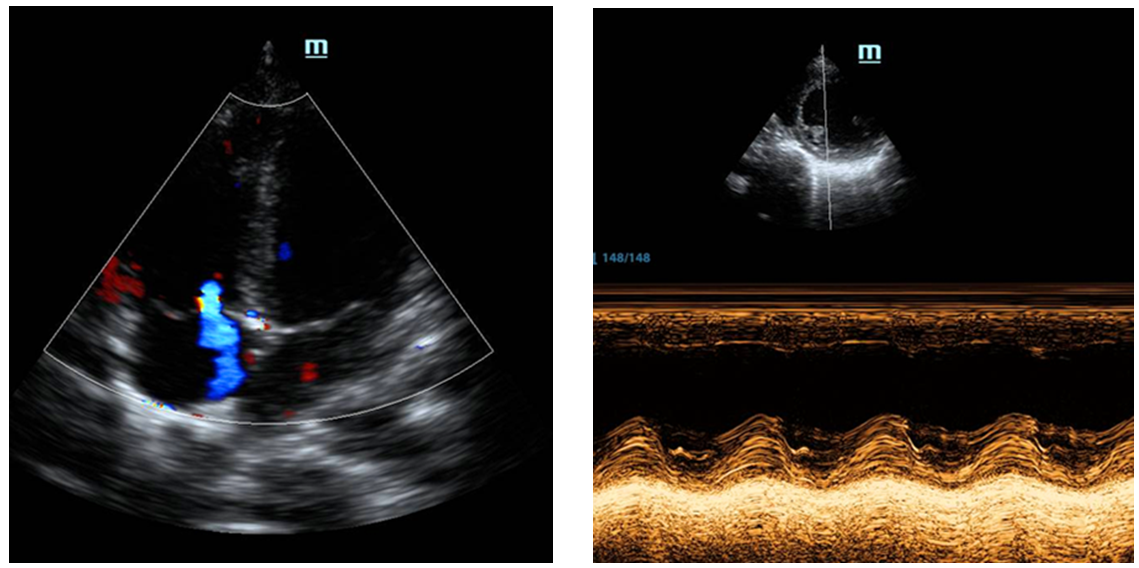

检查提示急性前壁心肌梗死(图1),急查心肌酶阳性,床旁心脏超声提示左室前壁运动幅度减低(图2),左室射血分数(LVEF)为45%。

图2 心脏超声提示左室前壁运动功能减低